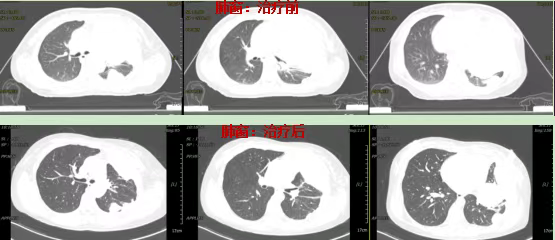

Lung window findings:

Pre-treatment: Significant compression and atelectasis of the left lung were observed.

Post-treatment: The left lung demonstrated complete re-expansion without evidence of pneumonitis or persistent atelectasis.